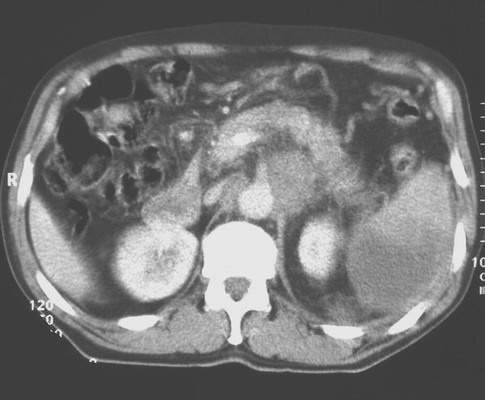

Das Bild zeigt ein CT eines diffus - großzelligen NHLs mit paraaortalen Herden und Milzbefall.

ACT diffus großzellig